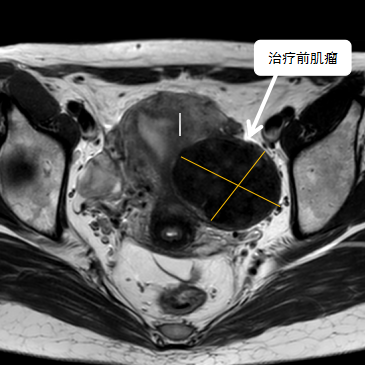

術(shù)前影像資料

經(jīng)過兩個(gè)月的藥物預(yù)處理,完善術(shù)前準(zhǔn)備,治療當(dāng)天陳主任帶領(lǐng)團(tuán)隊(duì)在3.0T磁共振清晰圖像引導(dǎo)下對子宮肌瘤進(jìn)行精準(zhǔn)消融,患者全程清醒,沒有明顯疼痛,經(jīng)過1個(gè)多小時(shí)的精細(xì)操作,手術(shù)非常成功,消融率接近90%,內(nèi)膜未見損傷!觀察一個(gè)小時(shí)后患者即自行回家。

術(shù)后即刻行增強(qiáng)磁共振檢查,顯示病變被消融近90%,內(nèi)膜未見損傷